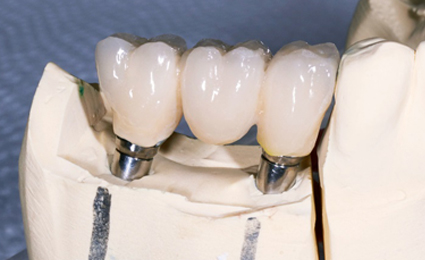

전체 임플란트

8개 이상의 임플란트를 수술하는 큰 수술이며, 환자의 구강구조를 정확히 파악해야 하기에 숙련도 높은 전문가의 식립이 필요합니다.